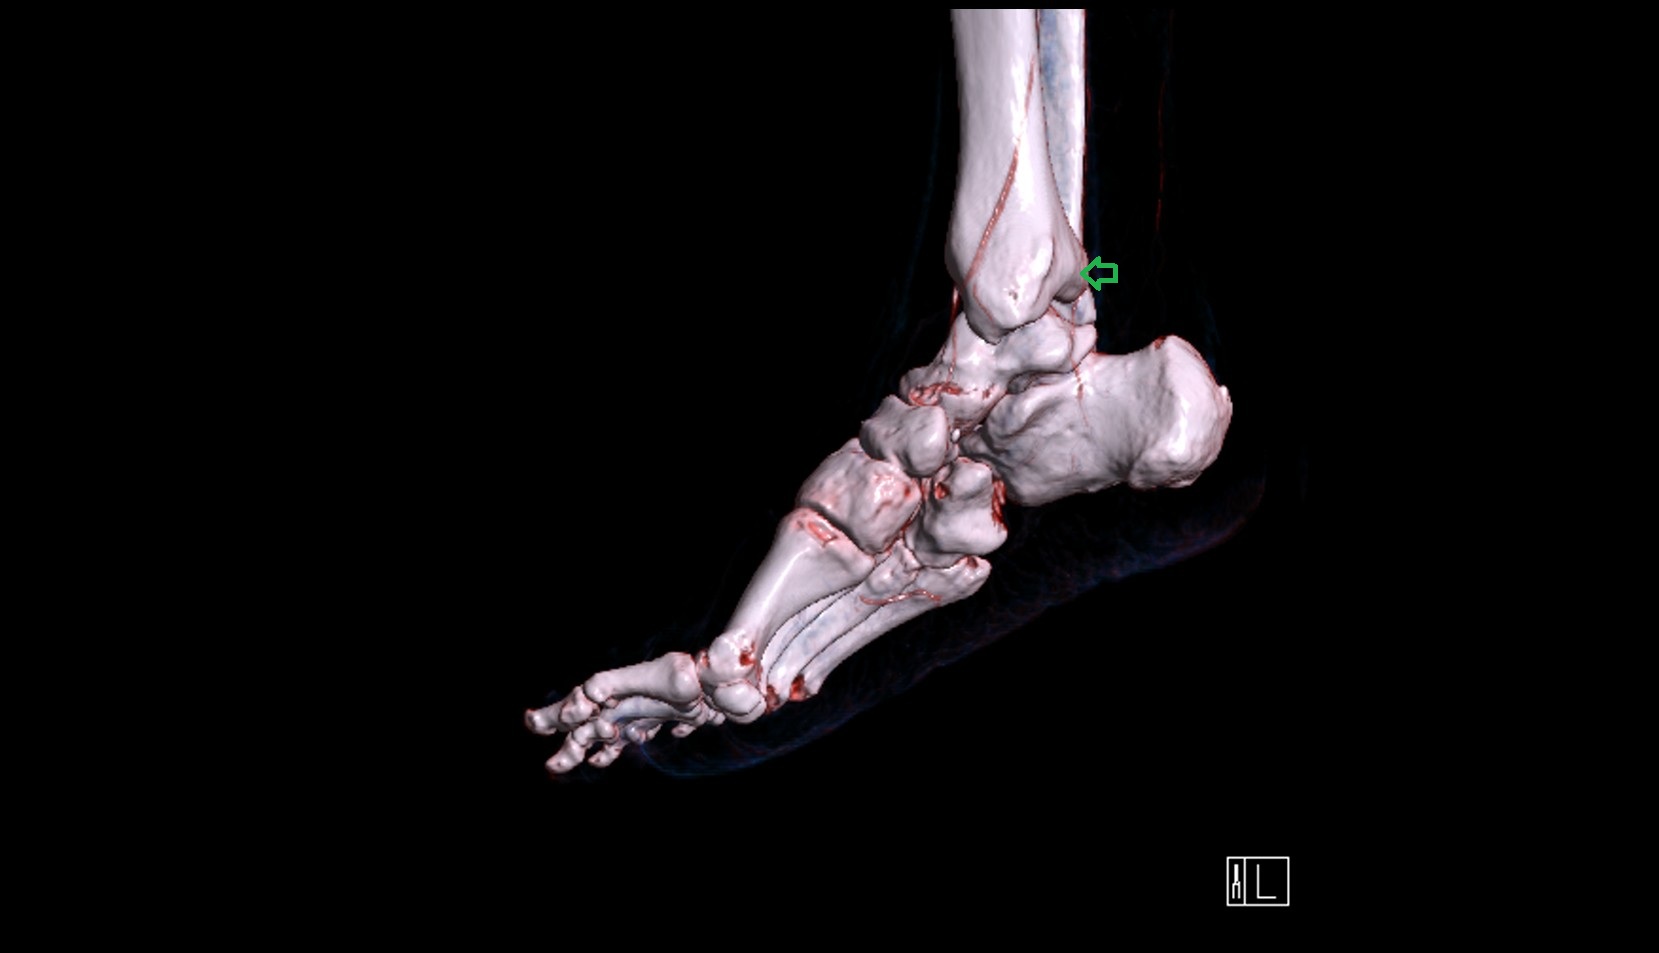

- Talus

- Head of talus

- Body of talus

- Neck of talus

- Calcaneus

- Medial malleolus

- Lateral malleolus

- Ankle joint